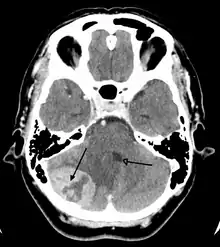

Imaging

Medical imaging plays a central role in the diagnosis of brain tumors. Early imaging methods – invasive and sometimes dangerous – such as pneumoencephalography and cerebral angiography have been abandoned in favor of non-invasive, high-resolution techniques, especially magnetic resonance imaging (MRI) and computed tomography (CT) scans,[39] though MRI is typically the reference standard used.[40] Neoplasms will often show as differently colored masses (also referred to as processes) in CT or MRI results.

- Benign brain tumors often show up as hypodense (darker than brain tissue) mass lesions on CT scans. On MRI, they appear either hypodense or isointense (same intensity as brain tissue) on T1-weighted scans, or hyperintense (brighter than brain tissue) on T2-weighted MRI, although the appearance is variable.

- Contrast agent uptake, sometimes in characteristic patterns, can be demonstrated on either CT or MRI scans in most malignant primary and metastatic brain tumors.

- Pressure areas where the brain tissue has been compressed by a tumor also appear hyperintense on T2-weighted scans and might indicate the presence a diffuse neoplasm due to an unclear outline. Swelling around the tumor known as peritumoral edema can also show a similar result.